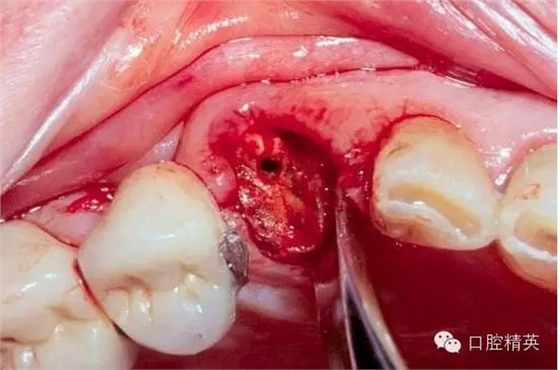

看看一個(gè)雙尖牙根的拔除 ,我常常對(duì)年輕的大夫說(shuō),我覺得難拔的不是下頜阻生智齒,而是有雙根的上頜雙尖牙,特別是一些正畸需要拔出的健康牙。

可以看到,luxator因?yàn)楹鼙〉娜?,能很容易插入牙周膜根向,從而獲得更穩(wěn)定的支點(diǎn)和更長(zhǎng)的動(dòng)力臂,不需要我們敲錘增隙,更不用去骨,從而保留更多的骨板。

拔除后軟硬組織的創(chuàng)傷都很小。